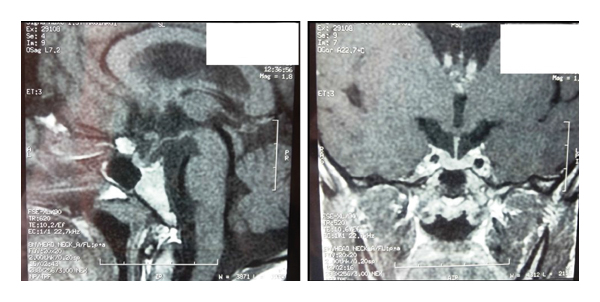

Magnetic resonance imaging (MRI) scan revealed a small and homogeneous anterior pituitary gland with a partially empty sella turcica. There was no tumor and the posterior lobe bright spot was normal. The pituitary stalk was median and thin (Figure 1).